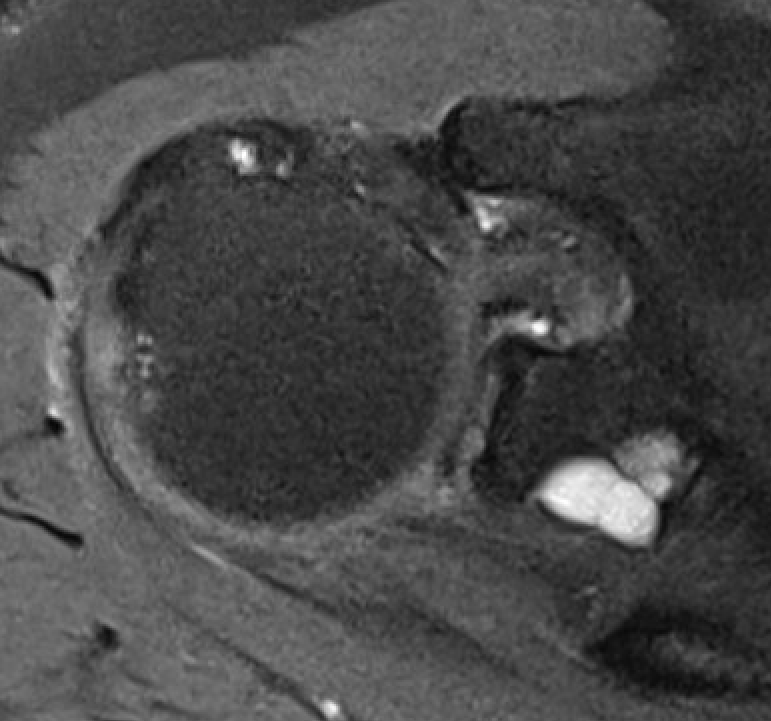

MRI

Spinoglenoid cyst

Spinoglenoid cyst with SLAP tear and posterosuperior labral tear

Posterior labral cysts secondary to glenohumeral OA